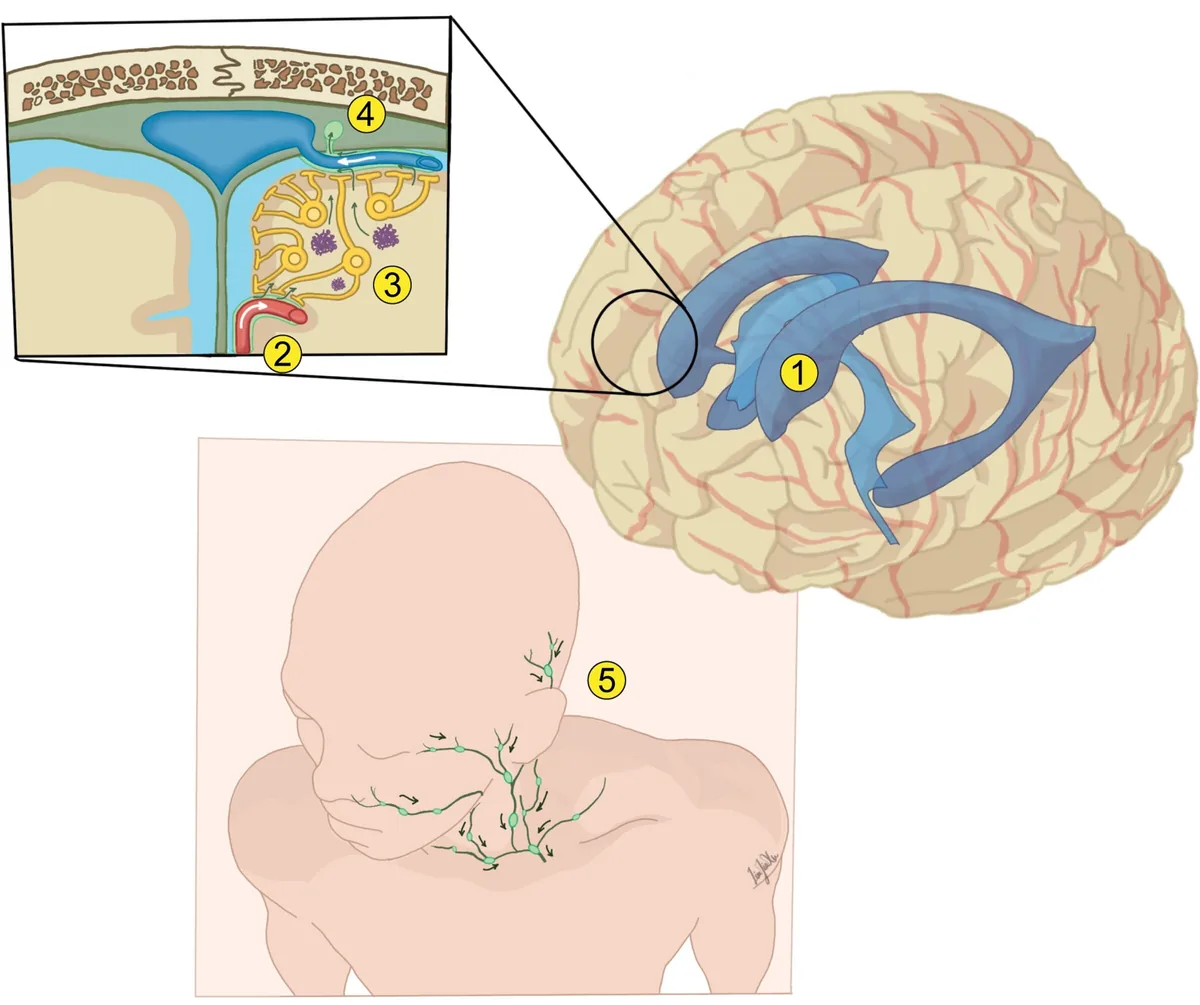

Key Mechanism Drives Neuronal Migration for Proper Cortical Layering

The cerebral cortex represents the outermost layer of the brain, playing a crucial role in advanced cognitive processes such as thinking, decision-making, and sensory perception. This essential brain region relies on a meticulously organized, multi-layered architecture to function effectively. For this structure to form correctly, freshly produced neurons must travel along specific routes and settle […]